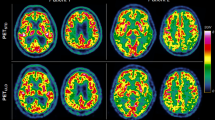

This study comprised manual reference segmentation of a wide range of tissues (18 different VOIs) of 13 whole-body scans by a Radiologist with 5 years of experience, see Fig. 1. These include the reference person selected for the Imiomics pipeline as well as the 12 subjects selected for the validation. In case of uncertainty about a segmentation, especially in the case of intestines (small and large) delineation, the opinion of a second radiologist with 30 years of experience was requested.

Illustration of reference tissue VOI segmentation. Each tissue evaluated has a different colour, also for left and right side. The colour are as follows: light beige (brain); light green (heart, left ventricle); red (liver); lime green (pancreas); purple (small intestine); beige (large intestine); light purple (right gluteal muscles); olive green (left gluteal muscles); blue (right thigh muscles); light blue (left thigh muscles); dark green (right calf muscles); yellow (left calf muscles). The other tissues are not shown in this slice.

The tissues evaluated in the analysis were: brain, including cerebellum (from the vertex to the last slice of the cerebellum hemispheres in coronal view); lungs (from apexes to bases in coronal view); heart (atria and ventricles in axial view); liver (from the dome to the last slice of the 6th segment in axial view); VAT (from the diaphragm to the sacral promontory in axial view); abdominal subcutaneous adipose tissue, SAT (analogous to VAT in axial view); pancreas (from the head to the tail in axial view); kidneys (from the upper pole to the lower pole in coronal view); bilateral gluteal muscles (maximus, medius and minimus in coronal view), thigh muscles (anterior, medial and posterior fascial compartments in sagittal view) and calf muscles (anterior, posterior and lateral compartments in sagittal view). The segmentations of the small and large intestines were performed by drawing the boundaries of the intestinal walls in axial view, after reaching a consensus between the two radiologists in the regions where the delineation of these organs was more equivocal, due to the overlap between intestinal loops and other anatomical structures or in the cases of breathing motion artifacts.